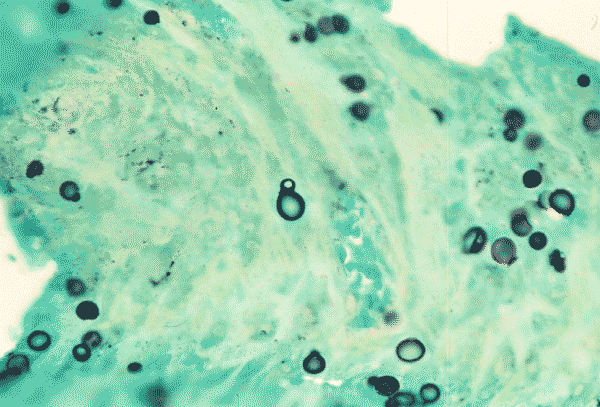

In this Gomori’s methenamine silver (GMS) stained section, yeasts with single broad based bud are present.